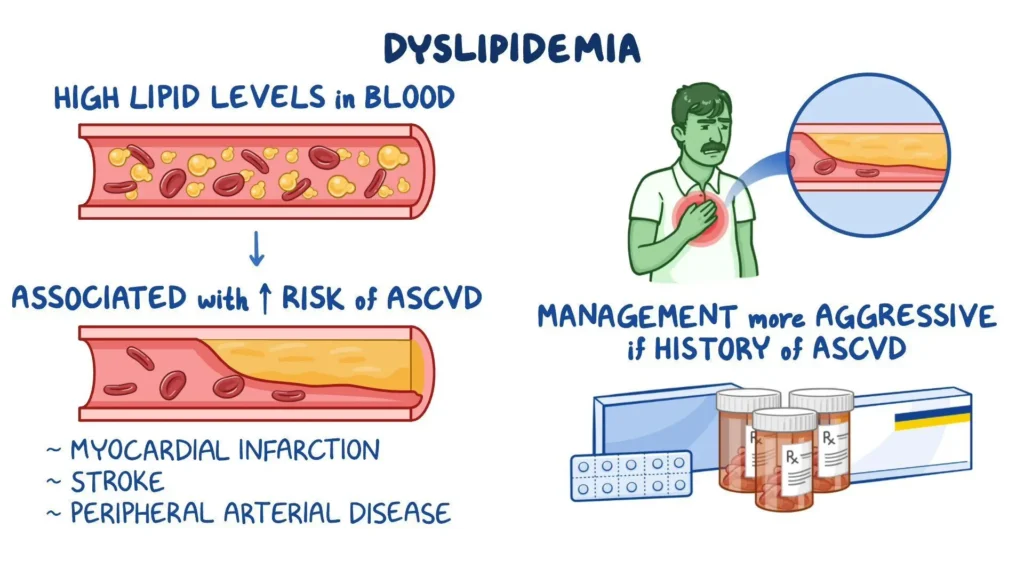

Ramai pernah mendengar istilah dyslipidemia, tetapi tidak semua memahami maksudnya. Dalam bidang perubatan, dyslipidemia maksudnya ialah keadaan di mana paras lipid dalam darah tidak normal, sama ada terlalu tinggi atau terlalu rendah. Lipid ini termasuk kolesterol (LDL, HDL, kolesterol total) dan trigliserida.

Keadaan ini sering dikaitkan dengan penyakit kardiovaskular seperti aterosklerosis, serangan jantung dan strok. Oleh itu, memahami pengertian dyslipidemia, punca, gejala dan rawatan sangat penting untuk menjaga kesihatan.

Jika tidak dirawat, dyslipidemia boleh menyebabkan:

Aterosklerosis – pengerasan arteri

Penyakit jantung koronari

Strok

Penyakit arteri periferi

Secara ringkas, dyslipidemia maksudnya ialah keadaan di mana paras kolesterol dan trigliserida tidak normal, sama ada terlalu tinggi atau terlalu rendah. Keadaan ini berisiko tinggi menyebabkan penyakit jantung dan strok.